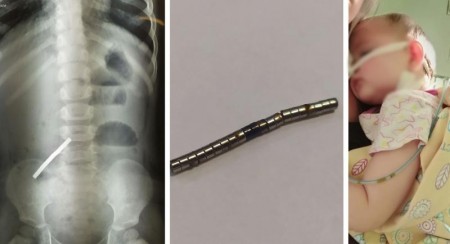

Отвёртка, гвозди и викинг. Красноярские хирурги показали, что они доставали из детей

Хирурги больницы №20 в Красноярске показали, какие предметы им доводилось извлекать из детей. В учреждении накопилась целая коллекция таких вещей, её ведут с 1986 года. Дети часто проглатывают монеты, пуговицы и детали от игрушек.

ЗдоровьеПроисшествияКрасноярск